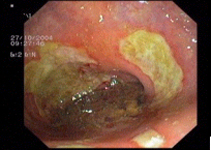

imagen3

Multiple rectal ulcer